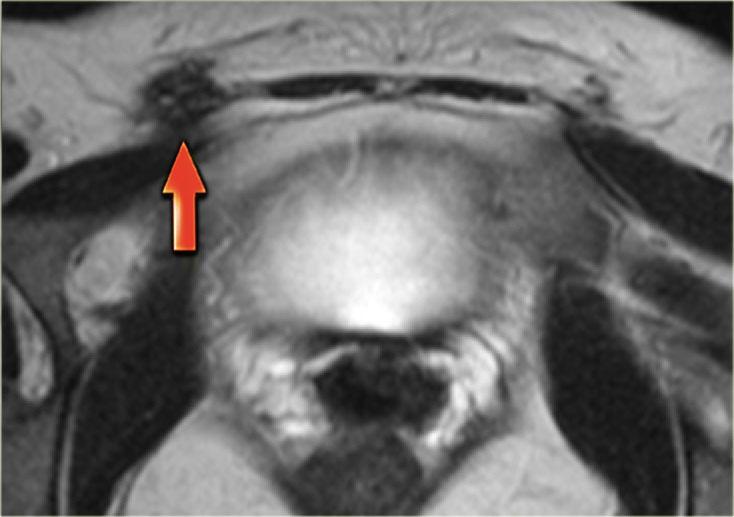

Bên trái là hình ảnh MRI của bệnh nhân bị lạc nội mạc tử cung thành bụng.

Trên chuỗi xung T2W, các tổn thương có tín hiệu đồng tín hiệu so với cơ, kèm theo các ổ nhỏ tăng tín hiệu, phản ánh các tuyến nội mạc tử cung bị giãn.

Trên ảnh T1W có xóa mỡ, các tổn thương có tín hiệu cao hơn một chút so với cơ (mũi tên).

Hình ảnh chuỗi xung T2W mặt cắt ngang bên trái minh họa một trường hợp lạc nội mạc tử cung thành bụng khác.